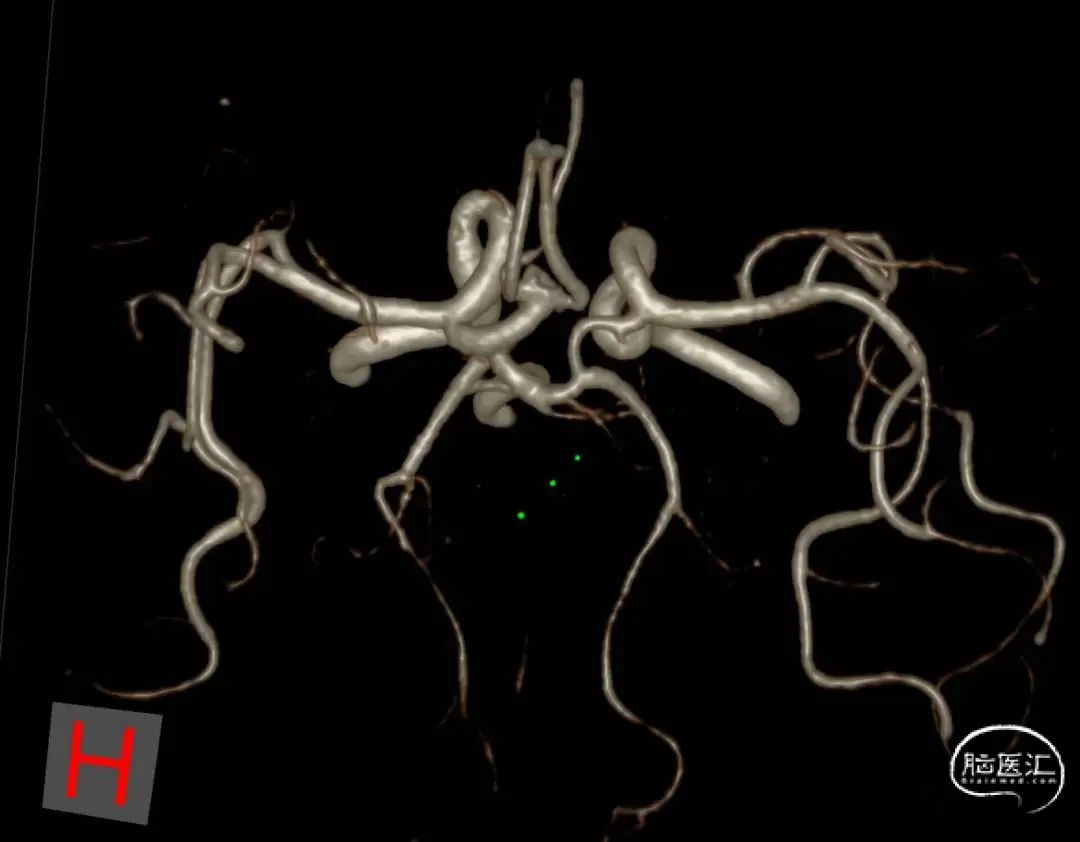

6.右侧颈内动脉C7段、左侧大脑中动脉M1段、基底动脉末端动脉瘤

动脉瘤一:基底动脉末端动脉瘤

(小脑上动脉瘤,侧壁)

动脉瘤一:基底动脉末端动脉瘤,由左侧大脑后动脉与左侧小脑上动脉瘤夹角处动脉瘤形成且为不规则状;瘤体上有子囊形成,左侧小脑上动脉从近心端瘤颈处动脉瘤瘤体上发出,动脉瘤与载瘤动脉近直角。

经测量可得动脉瘤宽度平均值为8.88mm,动脉瘤最小高度为7.71mm,瘤颈约为4.03mm。参考尺寸选择表,选择WEB™ SL 10*5,VIA™ 33微导管。